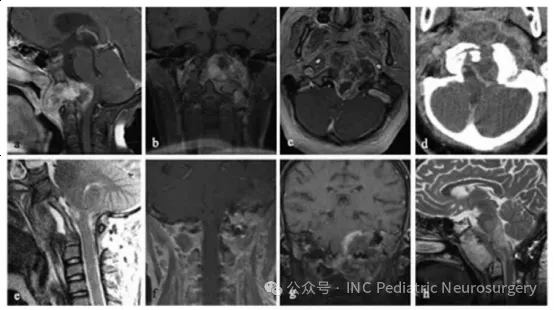

患者5

患者5于2003年就诊,11岁。主诉下位颅神经功能缺损持续2个月,伴鼻塞、斜颈(torticollis)以及右足阵挛(clonus)。影像学显示斜坡区巨大且具有破坏性的肿块,向左侧外延伸,侵及鼻咽部,并包绕左侧颈内动脉(图4)。

患者在经口活检后,接受了经口、经腭、经下颌联合入路的部分肿瘤切除手术,手术历时13小时,术后行枕骨–C3内固定融合术。病理结果显示为经典型病理,伴软骨样分化区域,MIB-1增殖指数30–50%,并p53阳性表达。

尽管进行了光子放疗,患者在诊断10个月后肿瘤进展。复发后接受5个月的Trabectedin(抗肿瘤化疗药物)治疗,但病情仍迅速进展,患者最终于诊断后15个月去世。

图4.患者5,巨大斜坡脊索瘤并脑干受压。

(a)术前矢状位T1加权MRI(增强);

(b)术前冠状位T1加权MRI(增强);

(c)术前轴位T1加权MRI(增强);

(d)术前轴位CT扫描;

(e)术后矢状位T1加权MRI(增强);

(f)术后冠状位T1加权MRI(增强);

(g)术后1年冠状位T1加权MRI(增强);

(h)术后1年矢状位T2加权MRI。